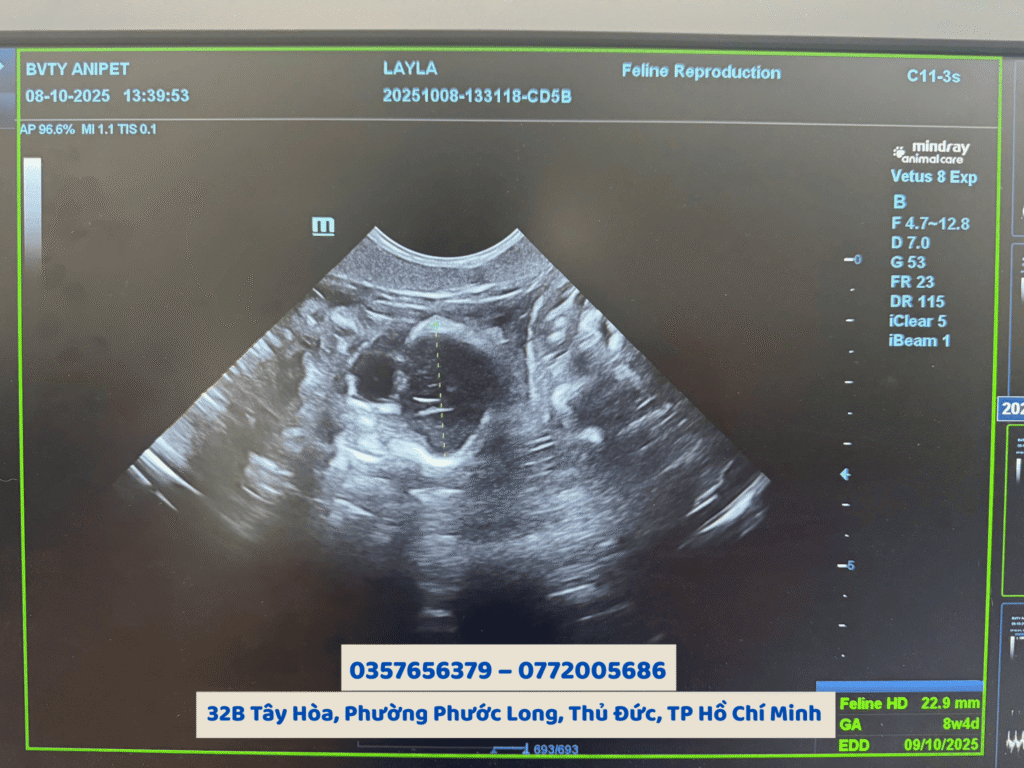

Tại Bệnh viện Thú y AniPet, quy trình siêu âm được thực hiện bằng thiết bị hiện đại, đảm bảo hình ảnh rõ nét và chẩn đoán chính xác, giúp chủ nuôi yên tâm chăm sóc đúng cách khi thú cưng mang bầu

Tại Bệnh viện Thú y AniPet, dịch vụ siêu âm thai cho chó mèo được thực hiện bởi đội ngũ bác sĩ thú y nhiều kinh nghiệm cùng hệ thống máy siêu âm kỹ thuật số hiện đại. Hình ảnh hiển thị rõ ràng, giúp bác sĩ dễ dàng nhận diện số lượng thai, vị trí và nhịp tim của từng bé con trong bụng chó mèo mẹ.

Việc siêu âm thai cho chó mèo định kỳ còn giúp theo dõi sự phát triển của thai nhi, đánh giá tình trạng nhau thai, nước ối, tim thai và phát hiện sớm các bất thường nếu có.